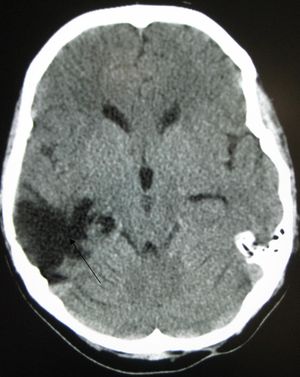

국소 손상의 한 종류인 뇌좌상은 뇌 조직이 찢어지거나 절단될 때 발생한다.[173] 특히 눈 위의 두개골 안쪽 뼈 돌출부 때문에 전전두엽 피질에서 흔하게 발생한다.[24] 뇌좌창은 뇌 조직에 멍이 드는 것으로, 혈액이 조직과 섞이는 상태를 말한다.[162] 반면 두개내 출혈은 혈액이 뇌 조직과 섞이지 않고 고이는 출혈을 의미한다.[173]

혈종 역시 국소 병변으로, 출혈로 인해 뇌 안이나 주변에 피가 고이는 것을 말한다.[7] 뇌 조직 자체에 출혈이 생기는 뇌내 출혈은 뇌막내성 병변이다. 뇌막외성 병변에는 다음과 같은 종류가 있다.[30]

- 경막외혈종: 두개골과 경막(뇌를 감싸는 가장 바깥쪽 뇌막) 사이에 피가 고이는 것.[7]

- 경막하혈종: 경막과 거미막 사이에 피가 고이는 것.[162]

- 지주막하 출혈: 거미막과 연막 사이에 피가 고이는 것.[162]

- 뇌실내 출혈: 뇌실계 안에 피가 고이는 것.[30]

응급 상황에서는 컴퓨터 단층촬영(CT)이 가장 선호되는 방사선 검사다. 신속하고 정확하며 널리 사용 가능하기 때문이다.[73] 손상이 진행되었는지 확인하기 위해 추후 CT 촬영을 실시할 수도 있다.[193]

자기공명영상(MRI)은 CT보다 더 자세한 정보를 보여주며 장기적인 예후에 대한 정보를 추가할 수 있다.[162] 특히 확산성 축삭 손상과 같은 손상 특징을 감지하는 데 CT보다 유용하다.[193] 하지만 MRI는 응급 상황에서는 출혈 및 골절 감지의 상대적 비효율성, 영상 획득 시간이 길다는 점, 기계 내 환자의 접근성 문제, 응급 치료에 사용되는 금속 물체와의 비호환성 등의 이유로 잘 사용되지 않는다.[162] 2012년 이후 MRI의 변형 기술로 고해상도 섬유 추적(HDFT)이 있다.[72]